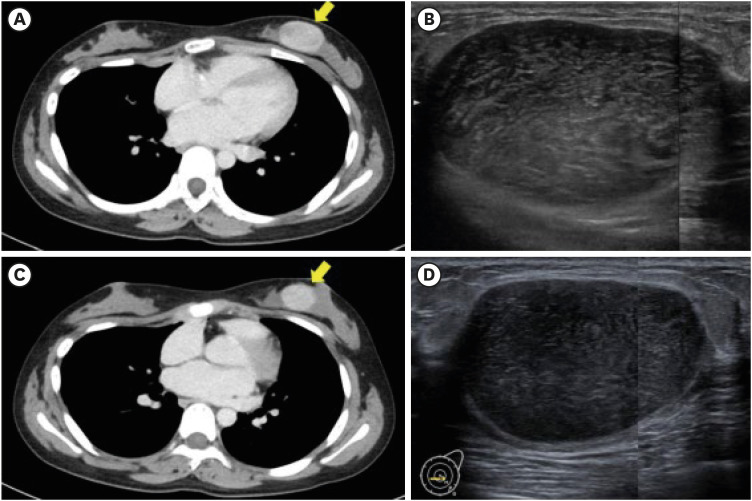

鳞状上皮细胞瘤(PT)是一种纤维上皮肿瘤,治疗方法是通过手术完全切除。包括放疗和化疗在内的辅助疗法对PT的疗效尚不明确,新辅助化疗(NAC)的应用也尚未确立。我们报告了一例患有急性淋巴白血病(ALL)的15岁女孩的病例,她通过计算机断层扫描、超声波检查和针刺活检后的组织学检查,偶然被诊断出左侧乳房有一个50毫米的边界PT。该患者在接受蒽环类化疗治疗后进行了乳腺切除术,术后肿瘤缩小。切除标本的组织病理学检查显示,化疗后有丝分裂活性和基质细胞减少。据我们所知,这是第一项报告化疗前和化疗后边缘PT样本组织病理学差异的研究。我们的研究结果表明,NAC可能会诱导边缘型PT发生变化,从而可能影响诊断和治疗决策。因此,有必要在这方面开展进一步研究。

Phyllodes tumors (PT) are fibroepithelial neoplasms that are treated by complete surgical excision. The effectiveness of adjuvant therapies, including radiotherapy and chemotherapy, for PT remains unclear, and the use of neoadjuvant chemotherapy (NAC) is yet to be established. We report a case of a 15-year-old girl with acute lymphatic leukemia (ALL) who was incidentally diagnosed with a 50-mm borderline PT in the left breast using computed tomography, ultrasonography, and histological examination following needle biopsy. Lumpectomy was performed after administration of anthracycline-based chemotherapy for ALL, resulting in tumor size reduction. Histopathological examination of the excised specimen demonstrated decreased mitotic activity and stromal cellularity post-chemotherapy. To our knowledge, this is the first study to report the histopathological differences in pre- and post-chemotherapy borderline PT samples. Our findings suggest that NAC may induce changes in borderline PT, potentially affecting diagnosis and treatment decisions. Hence, further investigation is warranted in this regard.